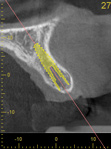

Fig 2. CBCT images: axial (Fig 2) and cross-sectional (Fig 3) views, and 3D reconstruction view (Fig 4) with virtually planned implant Nos. 8 and 9.

Figure 2

Fig 3. CBCT images: axial (Fig 2) and cross-sectional (Fig 3) views, and 3D reconstruction view (Fig 4) with virtually planned implant Nos. 8 and 9.

Figure 3